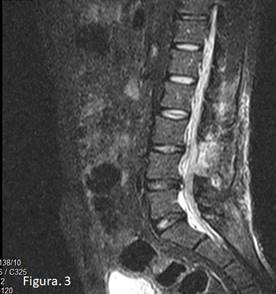

El estudio evolutivo por IRM de la columna lumbo sacra no mostró resto de la lesión operada con la restitución de los diámetros del canal, sin embargo, existe progresión de la degeneración de los discos intervertebrales de lumbares del tercero al quinto espacio (Figura 3).